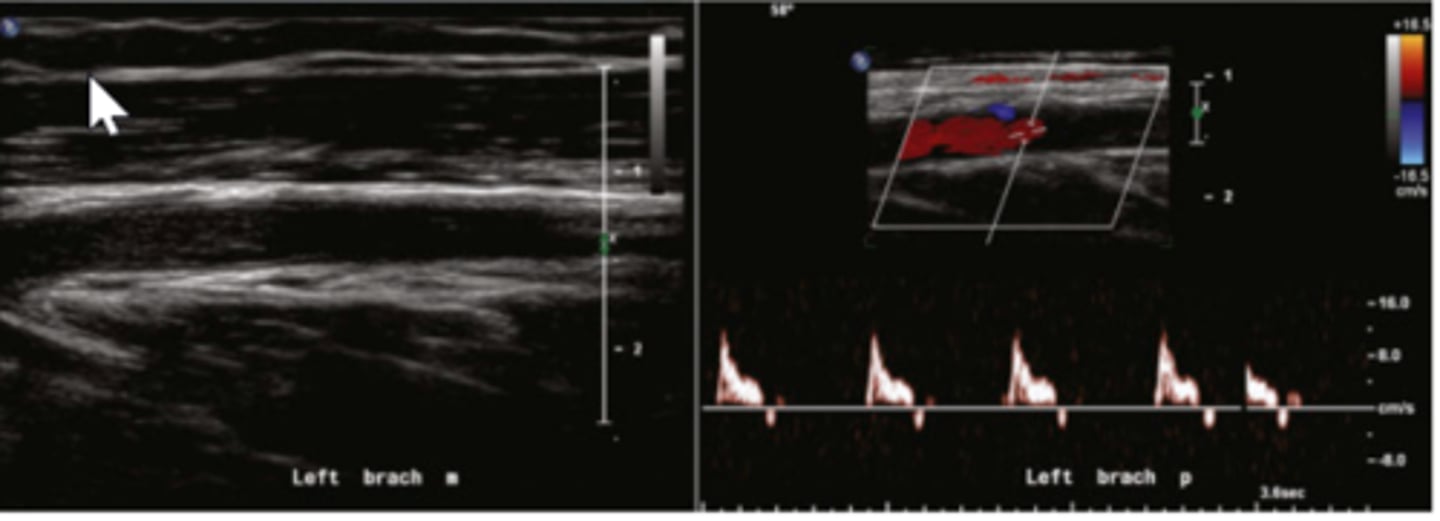

What do the below ultrasound images of the left brachial artery demonstrate? (ignore the mouse arrow on 2D image)

left brachial artery obstruction distal to the spectral Doppler sample site